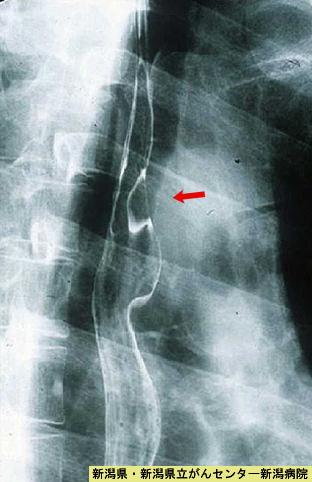

A case of cavernous hemangioma with calcification.

Niigata Pref., Niigata Cancer Center (Dr.秋山ら)

Non-epithelial tumors/Hemangioma, Lymphangioma

Esophagus/Upper third

X-ray

15 - 19